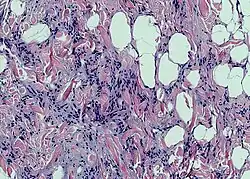

Клетки жировой ткани, накапливающие жир, называют адипоцитами. Одиночные адипоциты имеют шарообразную форму. Жировую ткань принято подразделять на белую и бурую согласно её цвету. Адипоцит белой жировой ткани содержит одну большую каплю нейтрального жира (такие адипоциты также называют унилокулярными), которая занимает центральную часть клетки и окружена тонким слоем цитоплазмы, в утолщённой части которого залегает уплощённое ядро. В цитоплазме адипоцитов содержатся в небольших количествах и другие липиды: холестерин, фосфолипиды, а также свободные жирные кислоты. Эти мелкие жировые включения особенно выражены у незрелых адипоцитов. Зрелый адипоцит имеет крупные размеры, от 50 до 150 мкм. Так как липиды вымываются ксилолом и другими растворителями, использующимися при приготовлении гистологических препаратов, унилокулярные адипоциты при рассмотрении с помощью светового микроскопа выглядят пустыми[3].

У новорождённых детей и некоторых животных (грызунов и животных, впадающих в спячку) выражена бурая жировая ткань. Адипоциты бурой жировой ткани, по сравнению с клетками белой жировой ткани, имеют больше митохондрий и вместо одной крупной жировой капли содержат множество мелких жировых включений в цитоплазме (такие адипоциты называют мультилокулярными[6]). Бурый цвет обеспечивается железосодержащими пигментами цитохромами, расположенными в митохондриях. Изменения бурой жировой ткани при голодании выражены меньше, чем белой[7].